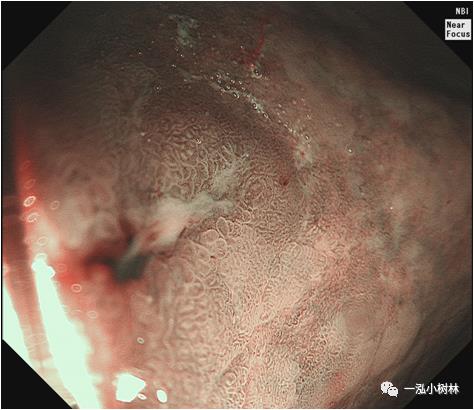

图4a 白光内镜:胃体下部高分化腺癌(Tub1)

图4b 白光内镜:胃体下部高分化腺癌(Tub1)

图4c NBI+ME:表面构造呈绒毛样,大小不等、形态不规则,边界清晰,诊断为0-IIc早期胃癌,分化程度:高分化腺癌(Tub1),深度:黏膜内。活检病理:高分化腺癌/高级别内瘤变。